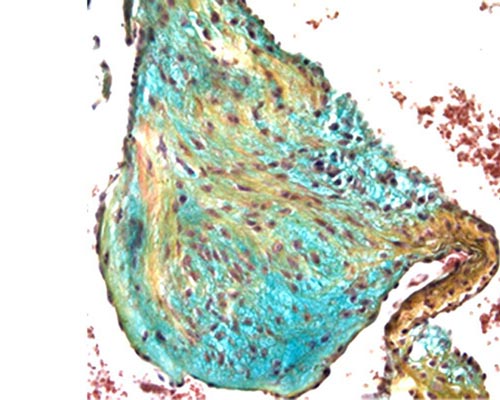

Dr. Mead is a trained developmental and molecular biologist with a keen focus on cardiovascular development and disease. His research centers on how changes in the extracellular matrix results in dysfunctional heart development and resulting congenital heart defects. Dr. Mead utilizes mouse models of congenital heart disease, biochemistry and proteomics to understand the molecular mechanisms underlying these diseases towards the development of therapeutic approaches. His current research focus is on the novel concept of inhibiting a protease that remodels fibrillin microfibrils in the aorta in an effort to identify a therapeutic for Marfan syndrome.